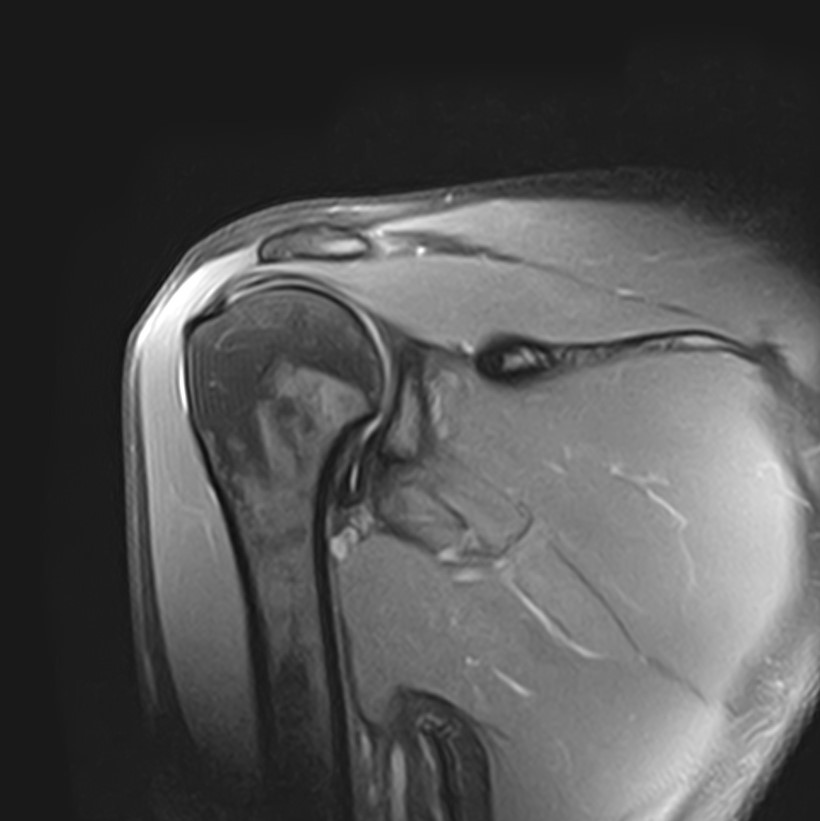

Метод МРТ позволяет оценить состояние всех анатомических областей плечевого сустава,  включая костную структуру, суставную капсулу, полость сустава с выстилающей его синовиальной оболочкой, связки, сухожилия, мышцы и окружающие мягкие ткани.

Магнитно-резонансная томография позволяет выявлять следующие заболевания плечевого сустава:

• Дегенеративно-дистрофические заболевания, в частности деформирующий остеоартроз, при котором происходит истончение хряща на фоне нарушения его питания. В результате развивается дисфункция сустава и деформация костных структур.

• Воспалительные заболевания с поражением как самого сустава (артрит), так и окружающих мягких тканей (синовит, бурсит, тендовагинит).

• Травмы плечевого сустава, различные переломы, при этом наиболее часто встречаются вывихи, что обусловлено анатомией сустава. Нередко травмы сустава с разрывом связок и сухожилий ведут в дальнейшем к развитию нестабильности плечевого сустава и могут стать причиной формирования привычных вывихов.